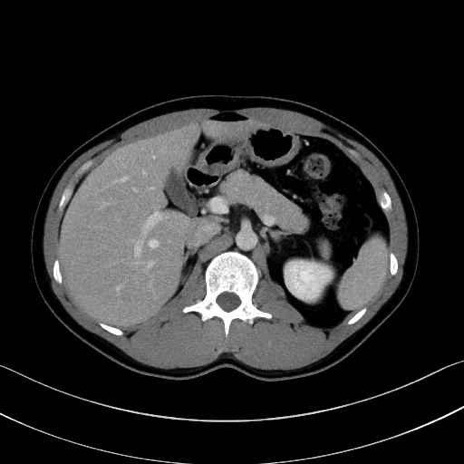

【症例】20歳代 男性 スクリーニング

■起始:典型的には腹腔動脈幹(celiac trunk)から左胃動脈・総肝動脈とともに三分岐し、脾動脈は左後上方へ向かう。

■走行:膵上縁または膵実質背側を蛇行しながら左方へ進み、膵尾部近傍で脾門へ至る。蛇行の程度は個体差が大きい。

■終枝:脾門部で複数の終末枝に分かれ、上極・下極枝や脾門枝群を形成する。胃短動脈群や左胃大網動脈はしばしば脾動脈から分岐する。